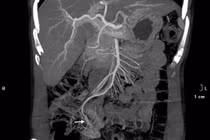

Sau khi hội chẩn, các bác sĩ nhận định đây là trường hợp nặng, nguy cơ chảy máu ồ ạt đe dọa tính mạng người bệnh. Bệnh nhi đã được can thiệp cấp cứu ngay sau đó. Sau 20 phút can thiệp với 5 coils ổ giả phình đã được loại bỏ hoàn toàn.

Bệnh nhi hết nôn máu, huyết động ổn, sau đó được chuyển về khoa Nhi tiếp tục điều trị tình trạng viêm tụy cấp.

| Hình ảnh sau nút mạch cho bệnh nhân. |